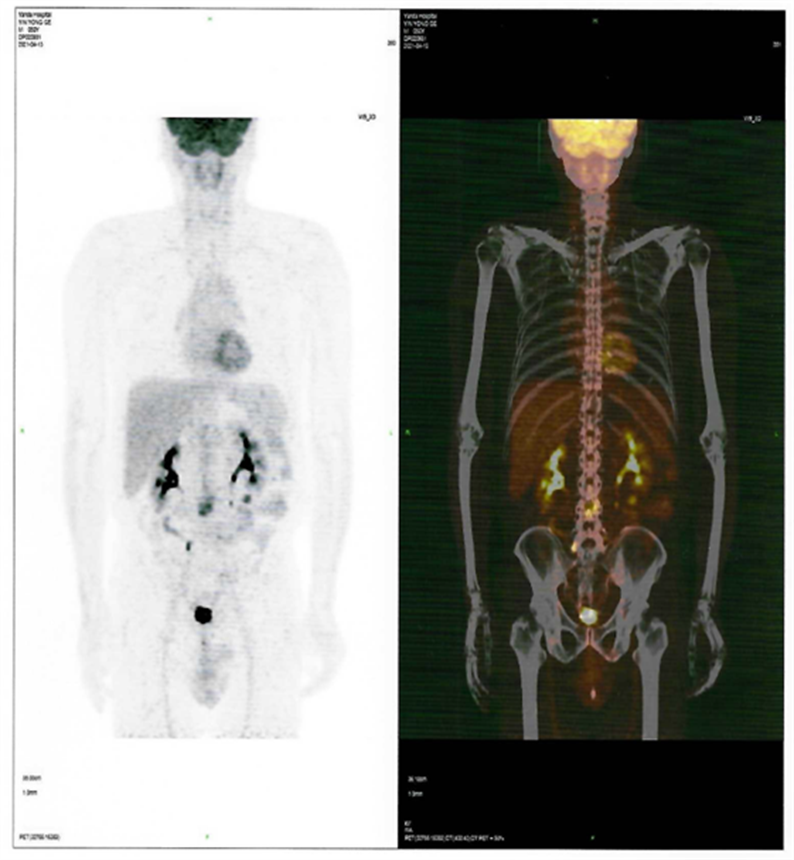

患者CAR-T 前后PET-CT檢查結(jié)果對(duì)比圖

CAR-T治療前

CAR-T治療后30天

2021年4月12日,患者來到燕達(dá)陸道培醫(yī)院,希望借助我院的CD7 CAR –T臨床試驗(yàn)項(xiàng)目獲得一線生機(jī)?;颊叱跞朐簳r(shí)PET-CT檢查提示:腫瘤細(xì)胞累及多處腸系膜和腹部肌肉軟組織;骨髓未累及。

回輸后一度出現(xiàn)了一級(jí)CRS反應(yīng),癥狀可控,5月26日,回輸后+28天復(fù)查PET-CT顯示CR(完全緩解)。預(yù)祝黃山先生接下來的治療一切順利!